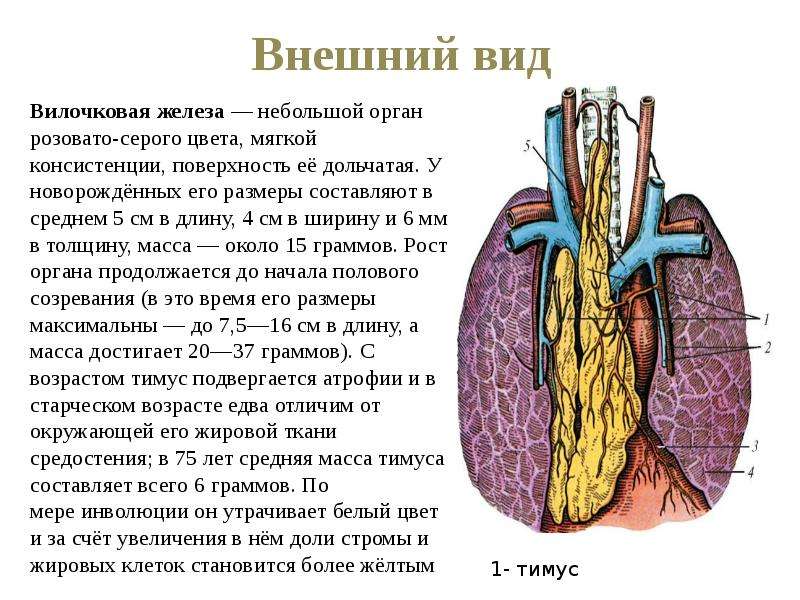

Фотографии вилочковой железы тимуса: структура и функции